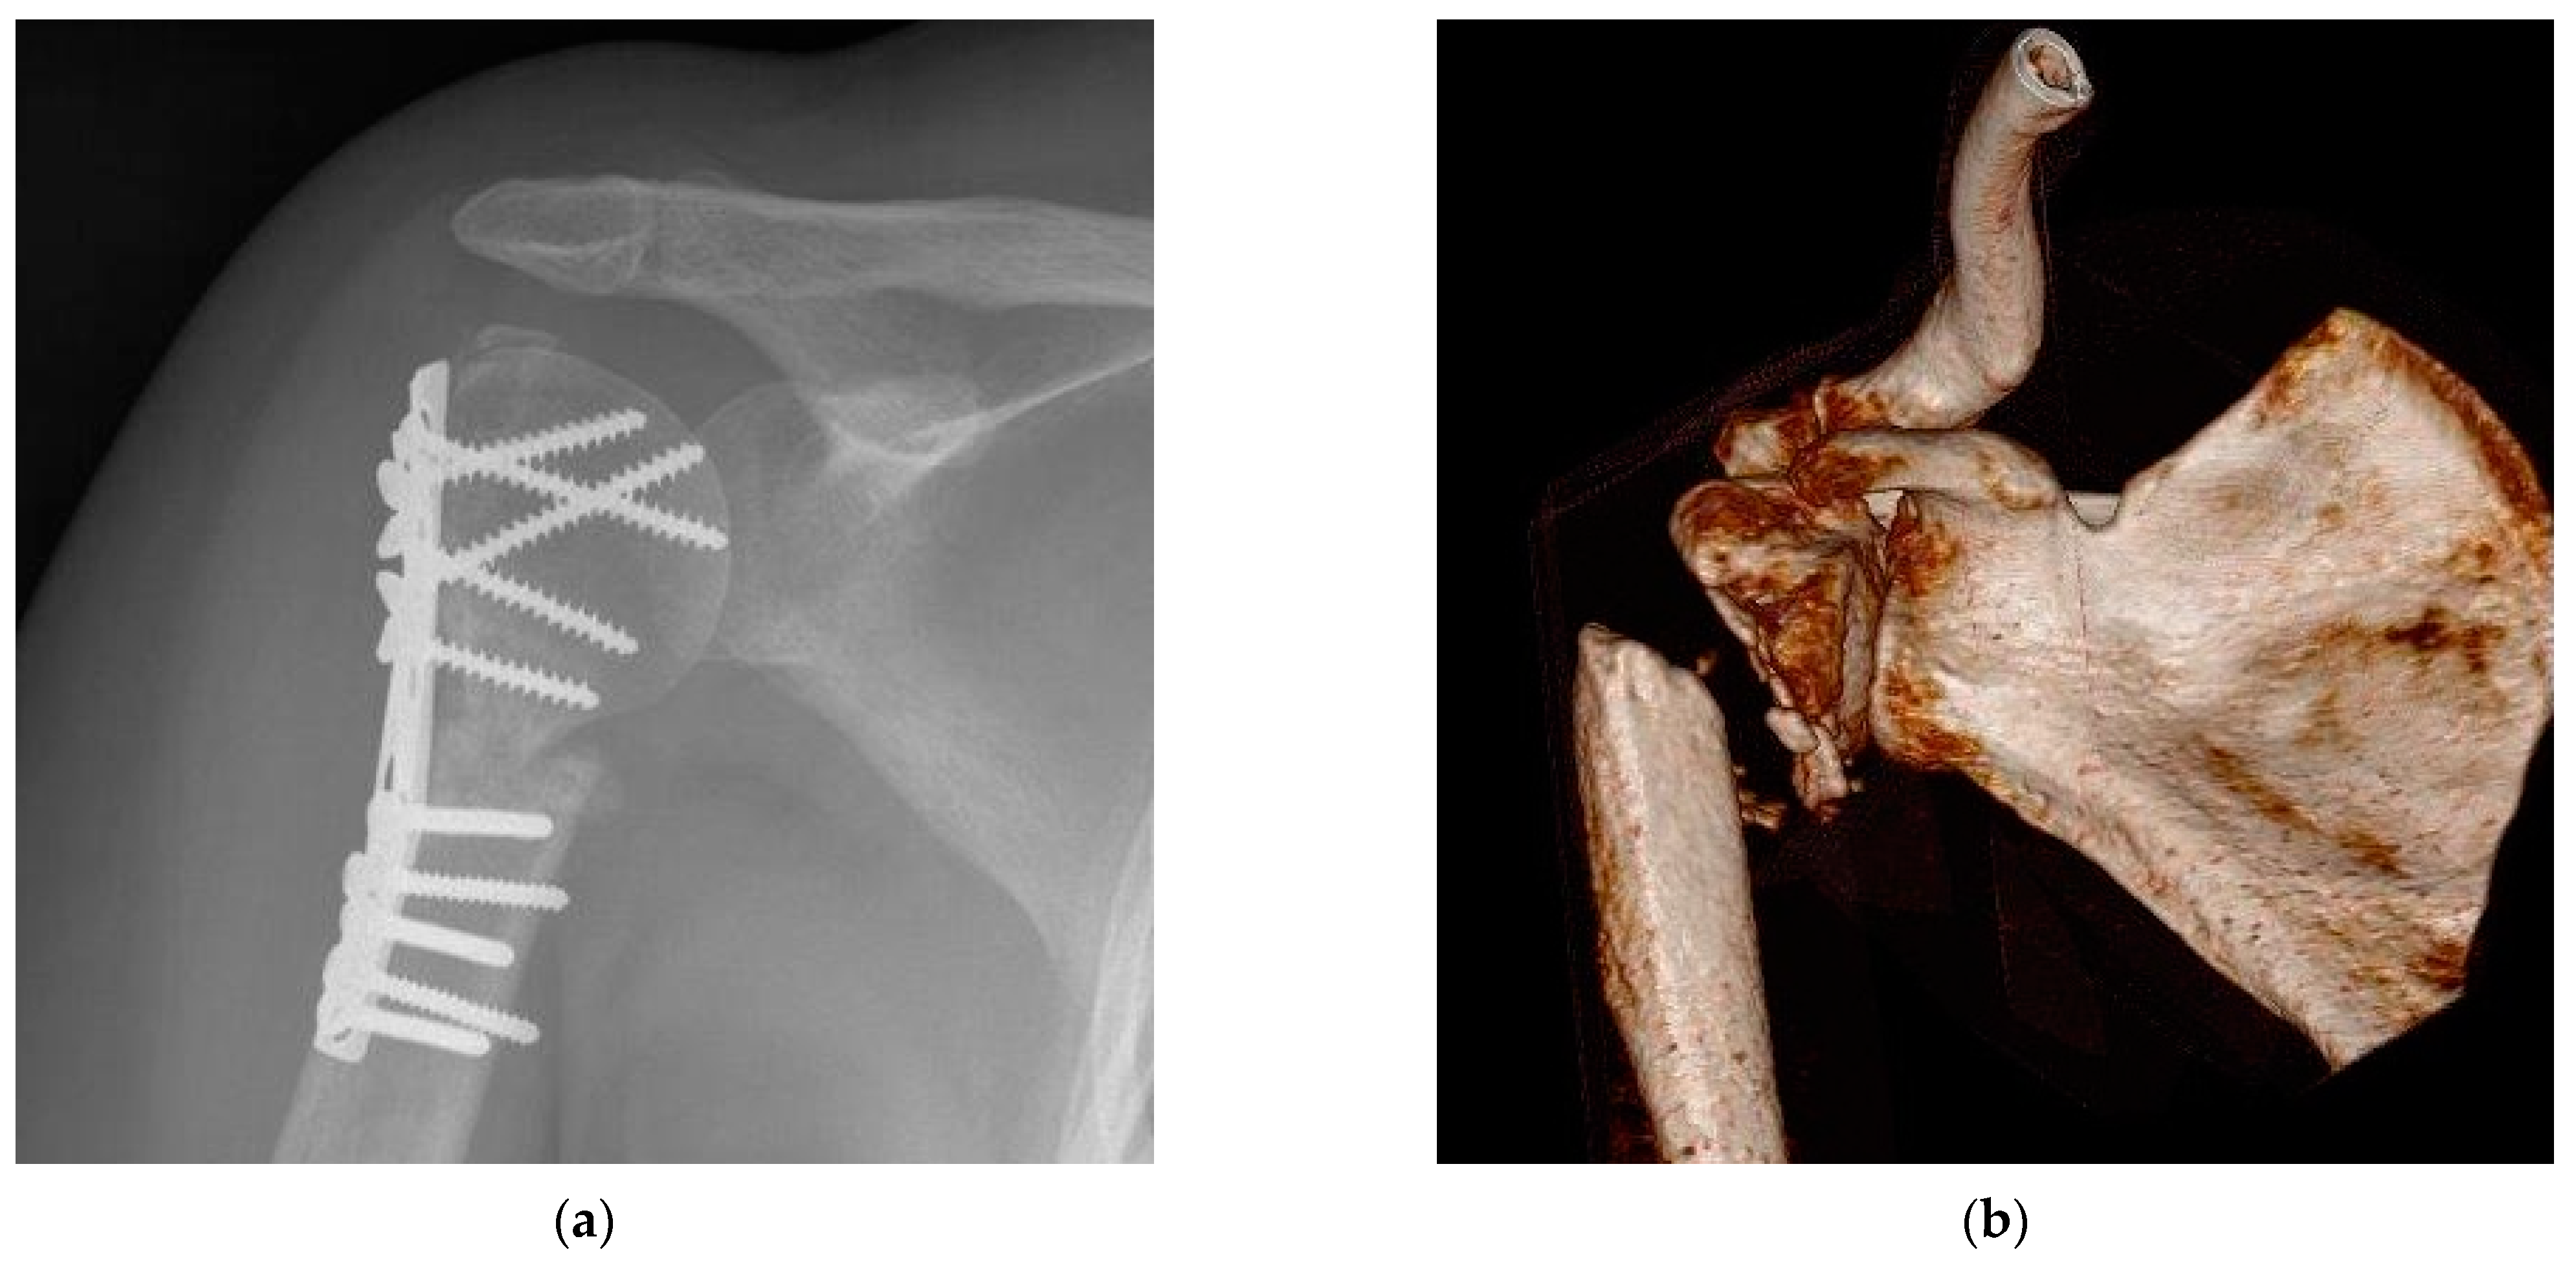

3. Discussion

4. Materials and Methods

4.4. Radiological Bone Healing Process

4.5. Postsurgical Complications